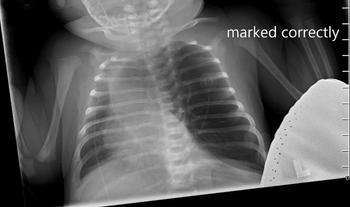

Case Studies